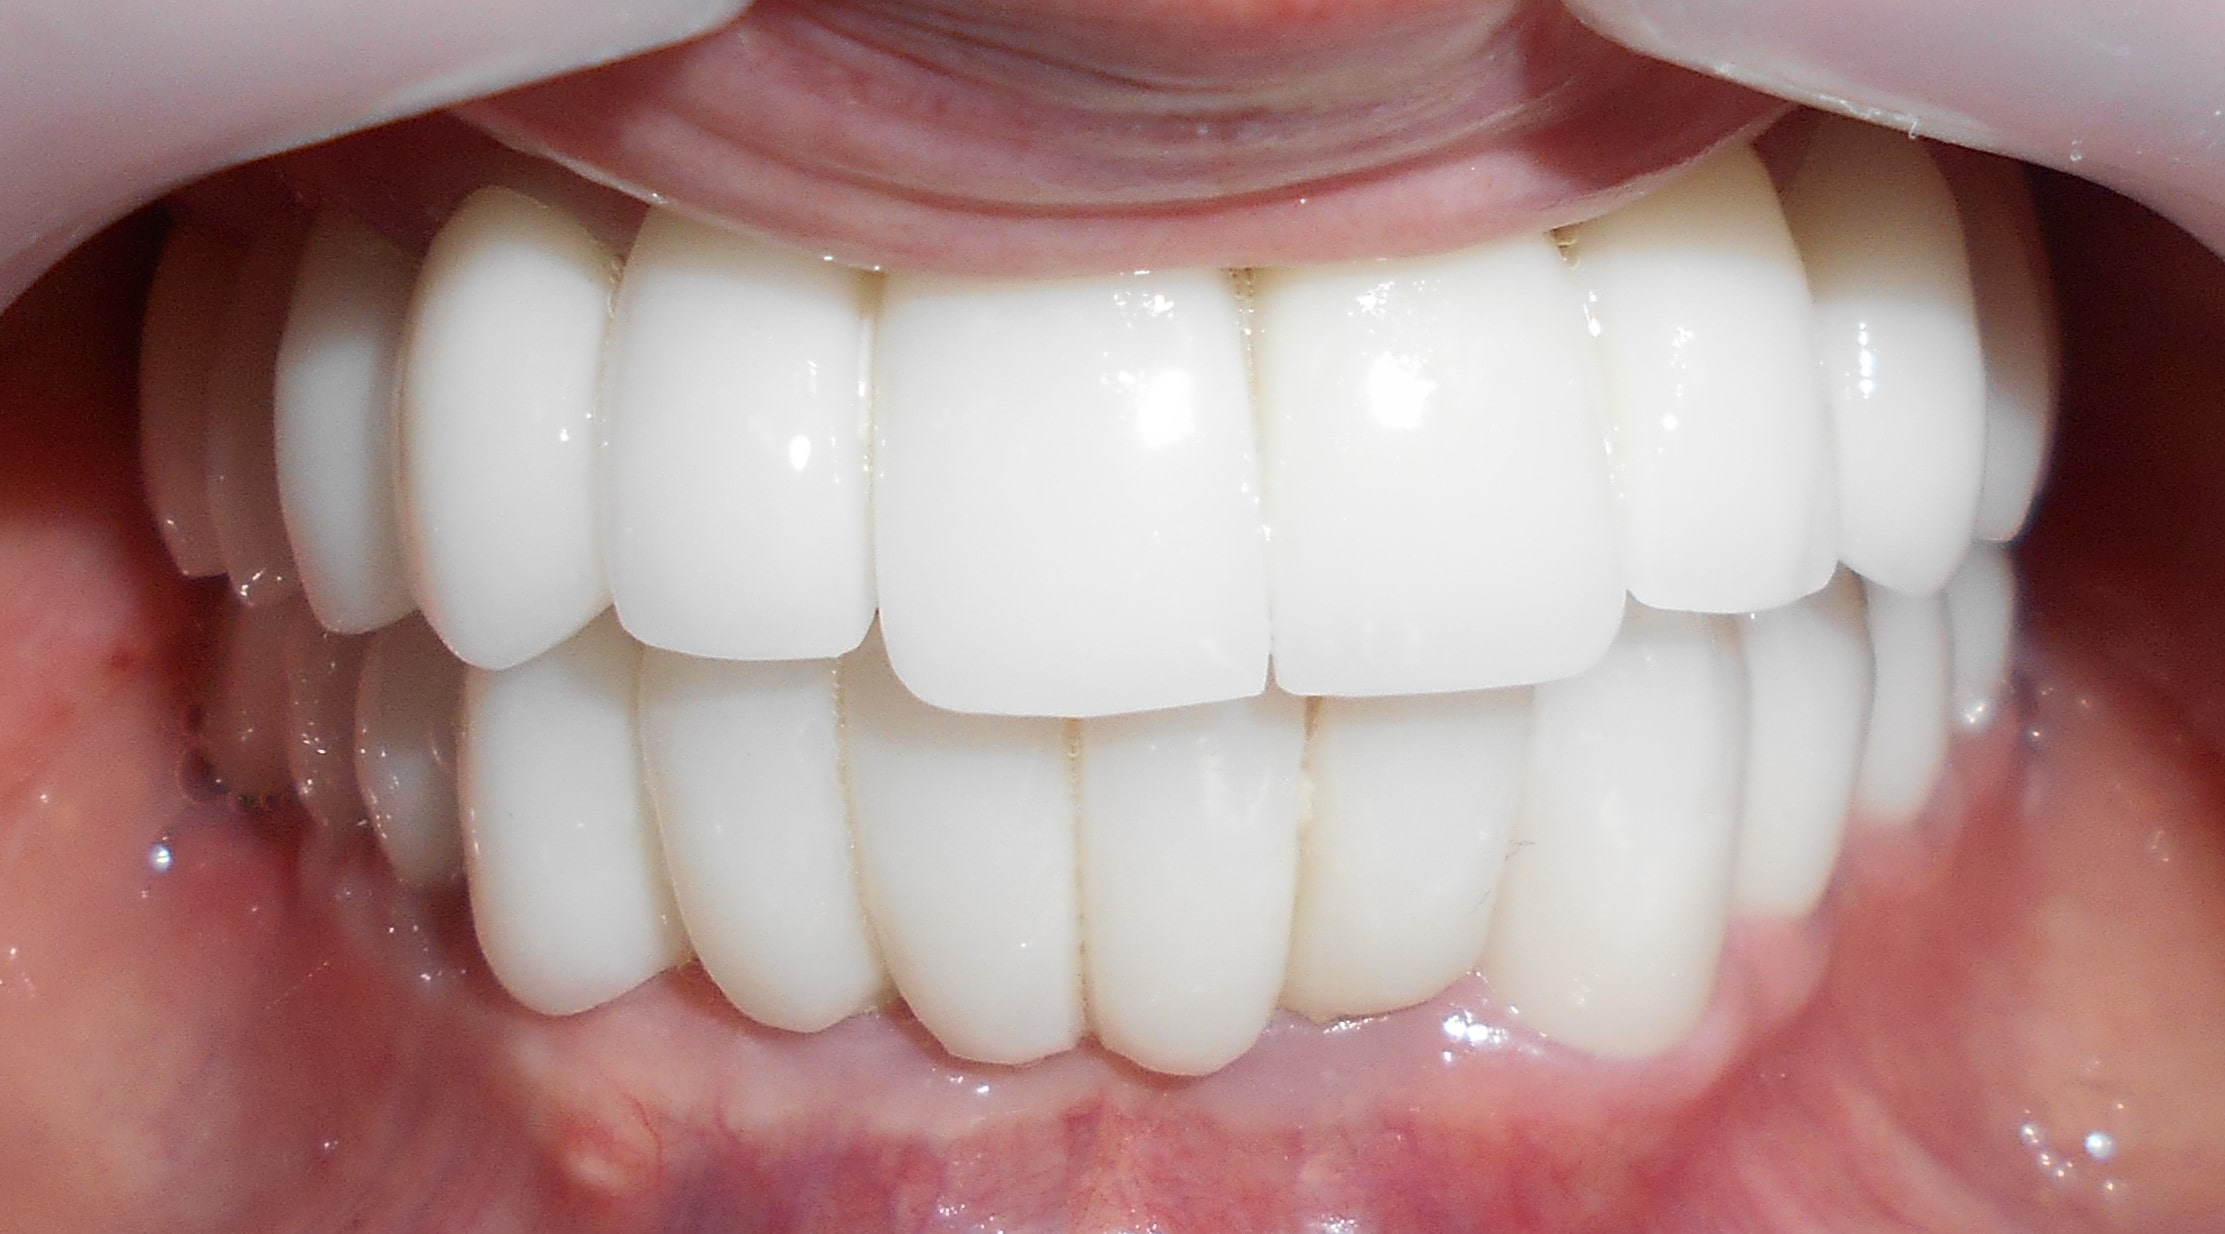

Pacijent iz Nemačke, kod koga smo estetsko i funkcionalno zbrinjavanje rešili cirkonijum keramičkim krunicama sa ugradnjom kratkih implantata u donjoj vilici zbog smanjene visine kosti, a u gornjoj vilici na levoj strani odmah nakon vađenja zuba je ugrađen standardni implantata na mesto izvađenog zuba i ugrađen je tuberopterigoidni implantat da se ne bi radila komplikovana sinus lift procedura koja bi produžila vreme završetka rada na godinu i više dana. Rad uspešno završen i pacijent nema nikakvih problema već pet godina.